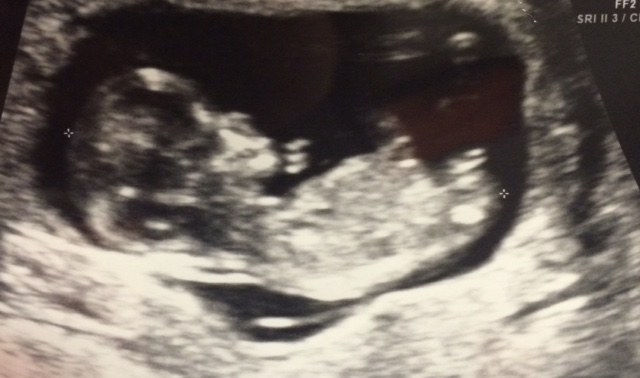

We had an ultrasound done to determine the baby's sex at 16 weeks. It was the technician's first day and I don't think she did a bad job but it took her a while to get a good shot and it seemed like she kept second guessing herself. When she first passed over the genitals it looked like I saw 3 lines, but then she pointed out what looked like the penis. What do you all think? For some reason I am second guessing her boy determination. I have a girl already and would be thrilled with either I just have this odd feeling that she was wrong. Any insight??